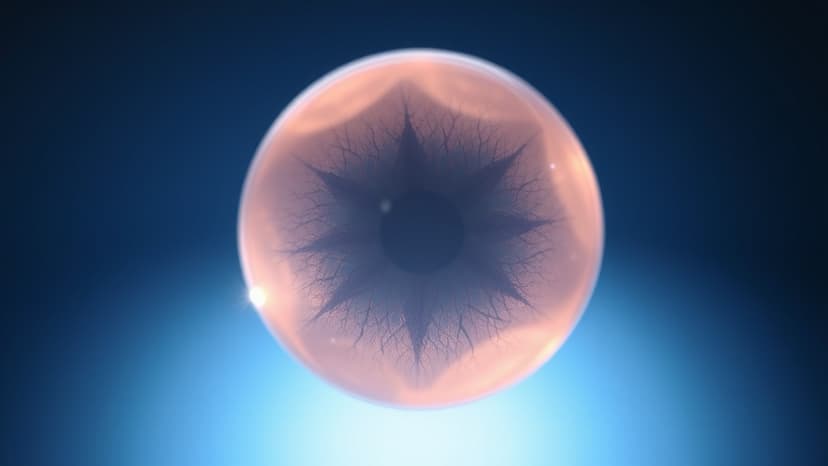

Eyes of Hope: 17,675 See Again Through Donation

Over the past 24 years, the Eye Bank Society of Rajasthan has enabled 17,675 visually impaired individuals to see again through eye donation. Established in 2002, the organization has collected a total of 27,307 corneas, facilitating free corneal transplants for numerous beneficiaries.